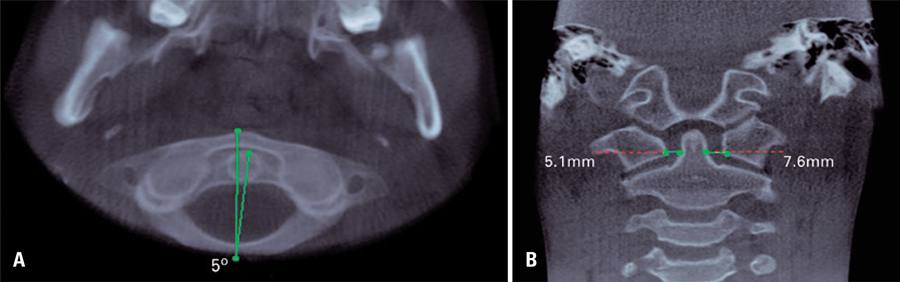

Rotatory instability is characterized by the rotation between two vertebral bodies, and it constitutes the most common cause of torticollis in children.(-) This prevalence occurs because of specific anatomic characteristics of childhood, such as disproportion between head-neck, underdeveloped cervical musculature, laxity of the joint capsule, ligament elasticity and horizontal shape of the articular facets between atlas and axis vertebrae.(-) This condition can occur due to inflammation/infection(,,) or trauma,(,,,) or because of neurogenic or idiopathic origin.()

The diagnosis includes clinical and imaging exam.(,) Among imaging exams of bone tissue, radiographies in anteroposterior and lateral projections are of limited use because they do not enable a precise visualization of this alteration, due to difficulties in positioning patients (head offset or source of X-rays, and overlap of structures), leading to radiographic interpretation challenges.(,,) Computed tomography is considered the gold standard procedure.(,,) Images of tridimensional reconstruction provides a global visualization of rotation, therefore helping to establish the diagnosis.(,,) In addition, the magnetic resonance image can also be requested to evaluate the risk of vascular-nervous bundle compromising and injuries of the ligaments adjacent to vertebrae.(,-)